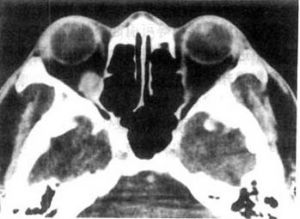

甲狀腺眼病CT表現:

1.雙側多發眼肌增粗,肌腹明顯,肌腱常不受累,保持尖削狀。偶見單側。病變眼外肌中度增強,邊緣光滑銳利。常見眼肌受累順序為下直肌與內直肌-眼上肌群-外直肌。

2.球後脂肪增加,眼球前移,視神經牽拉變直,略變細,眼外肌可呈輕度弧形外凸移位。

3.眶壁無侵蝕。